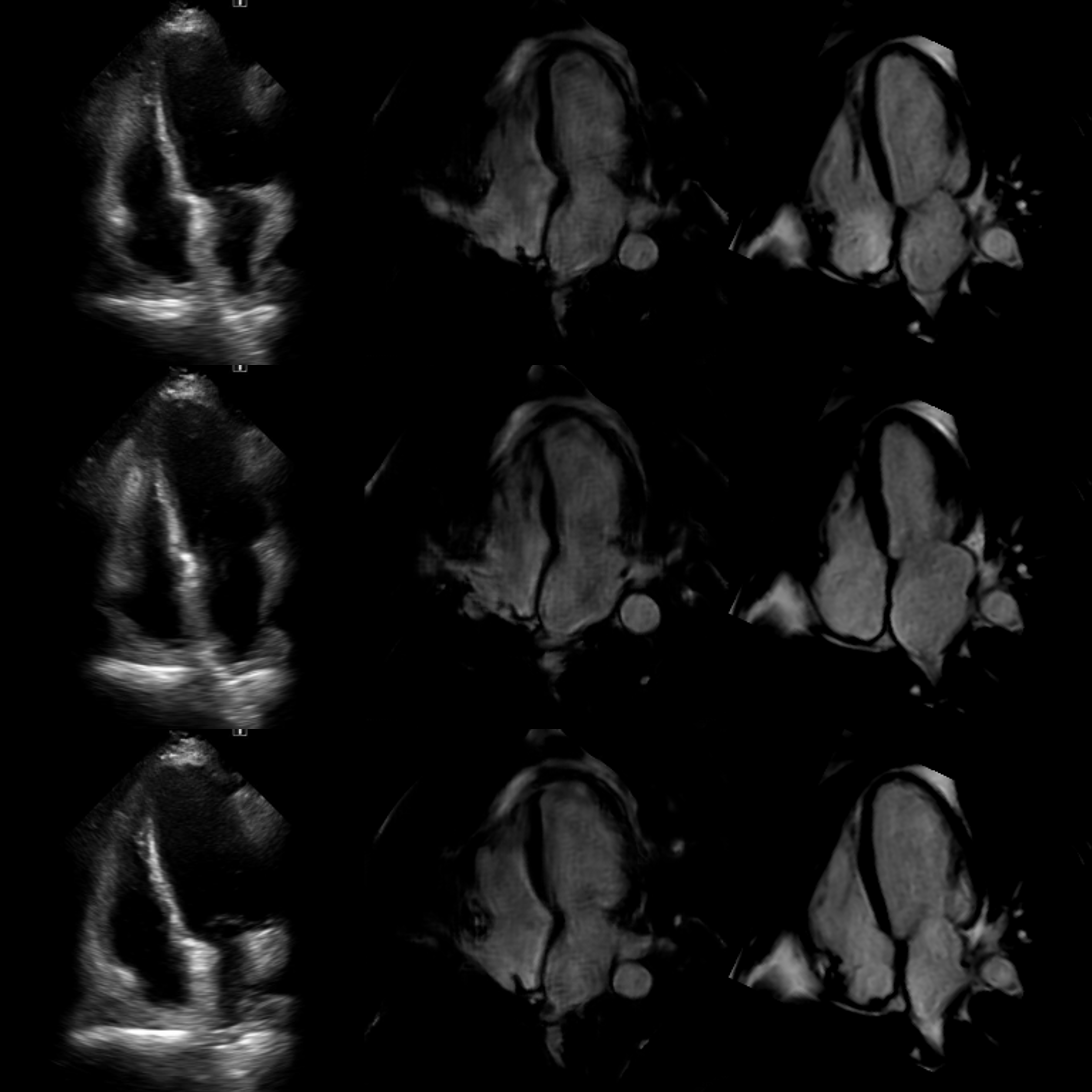

Refer to captionABC

Figure 19: Patient 22: Comparison of echocardiography (Column A), synthetic cardiac MRI (Column B), and real cardiac MRI (Column C) images. Echocardiography images show 3 different phases of one heartbeat, with corresponding synthetic and real cardiac MRI views.

Figure 20: Patient 29: Comparison of echocardiography (Column A), synthetic cardiac MRI (Column B), and real cardiac MRI (Column C) images. Echocardiography images show 3 different phases of one heartbeat, with corresponding synthetic and real cardiac MRI views.